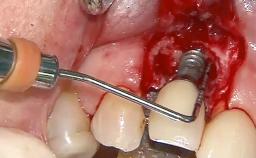

Surgical Management of Peri-Implantitis: Removal of Implant Due to Recurrent Infection Using an Implant-Retrieval Tool

Despite anti-infective surgical treatment, some patients may experience recurrent infection and progressive bone loss requiring additional treatment. This case describes a conservative approach using an implant retrieval tool without the need for excessive bone removal or use of a trephine.

A 65-year-old female patient was referred to the periodontist for assessment and management of infection associated with an implant at site 12. The general dentist had noted suppuration on probing during examination.